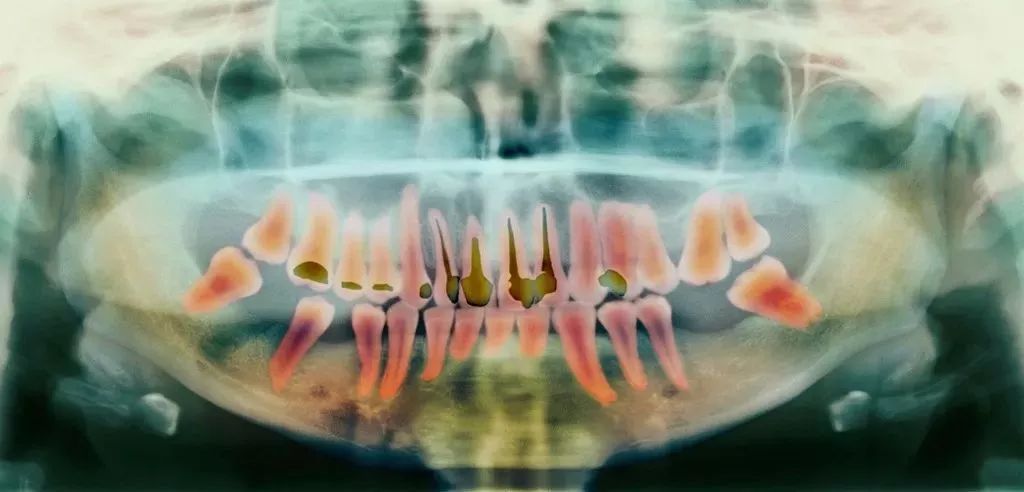

这是目前最有效、最常见的治疗牙髓病和根尖周病的方式,可以消除牙齿内部炎症及其病变源,

蛀牙坏到牙齿内部,牙髓或细菌感染引起了急/慢性牙髓炎;

牙髓由于长期刺激或其它原因造成的死髓牙;

意外磕碰、外伤,导致牙根尖血管断裂引起牙神经暴露;

其过程就是先将牙齿内部坏死的牙髓清理干净,再放入永久性消炎杀菌的药物,

要知道,牙齿龋坏最终会导致疼痛难忍,其实就是伤到牙神经了。

出了问题的牙神经会在牙齿内部腐坏、发酵,造成严重的感染和疼痛。

根管治疗后的牙齿,失去了来自牙髓的营养供应,就像失去树根的树木一样,

慢慢枯萎变得脆弱、颜色灰暗,也更容易发生劈裂。